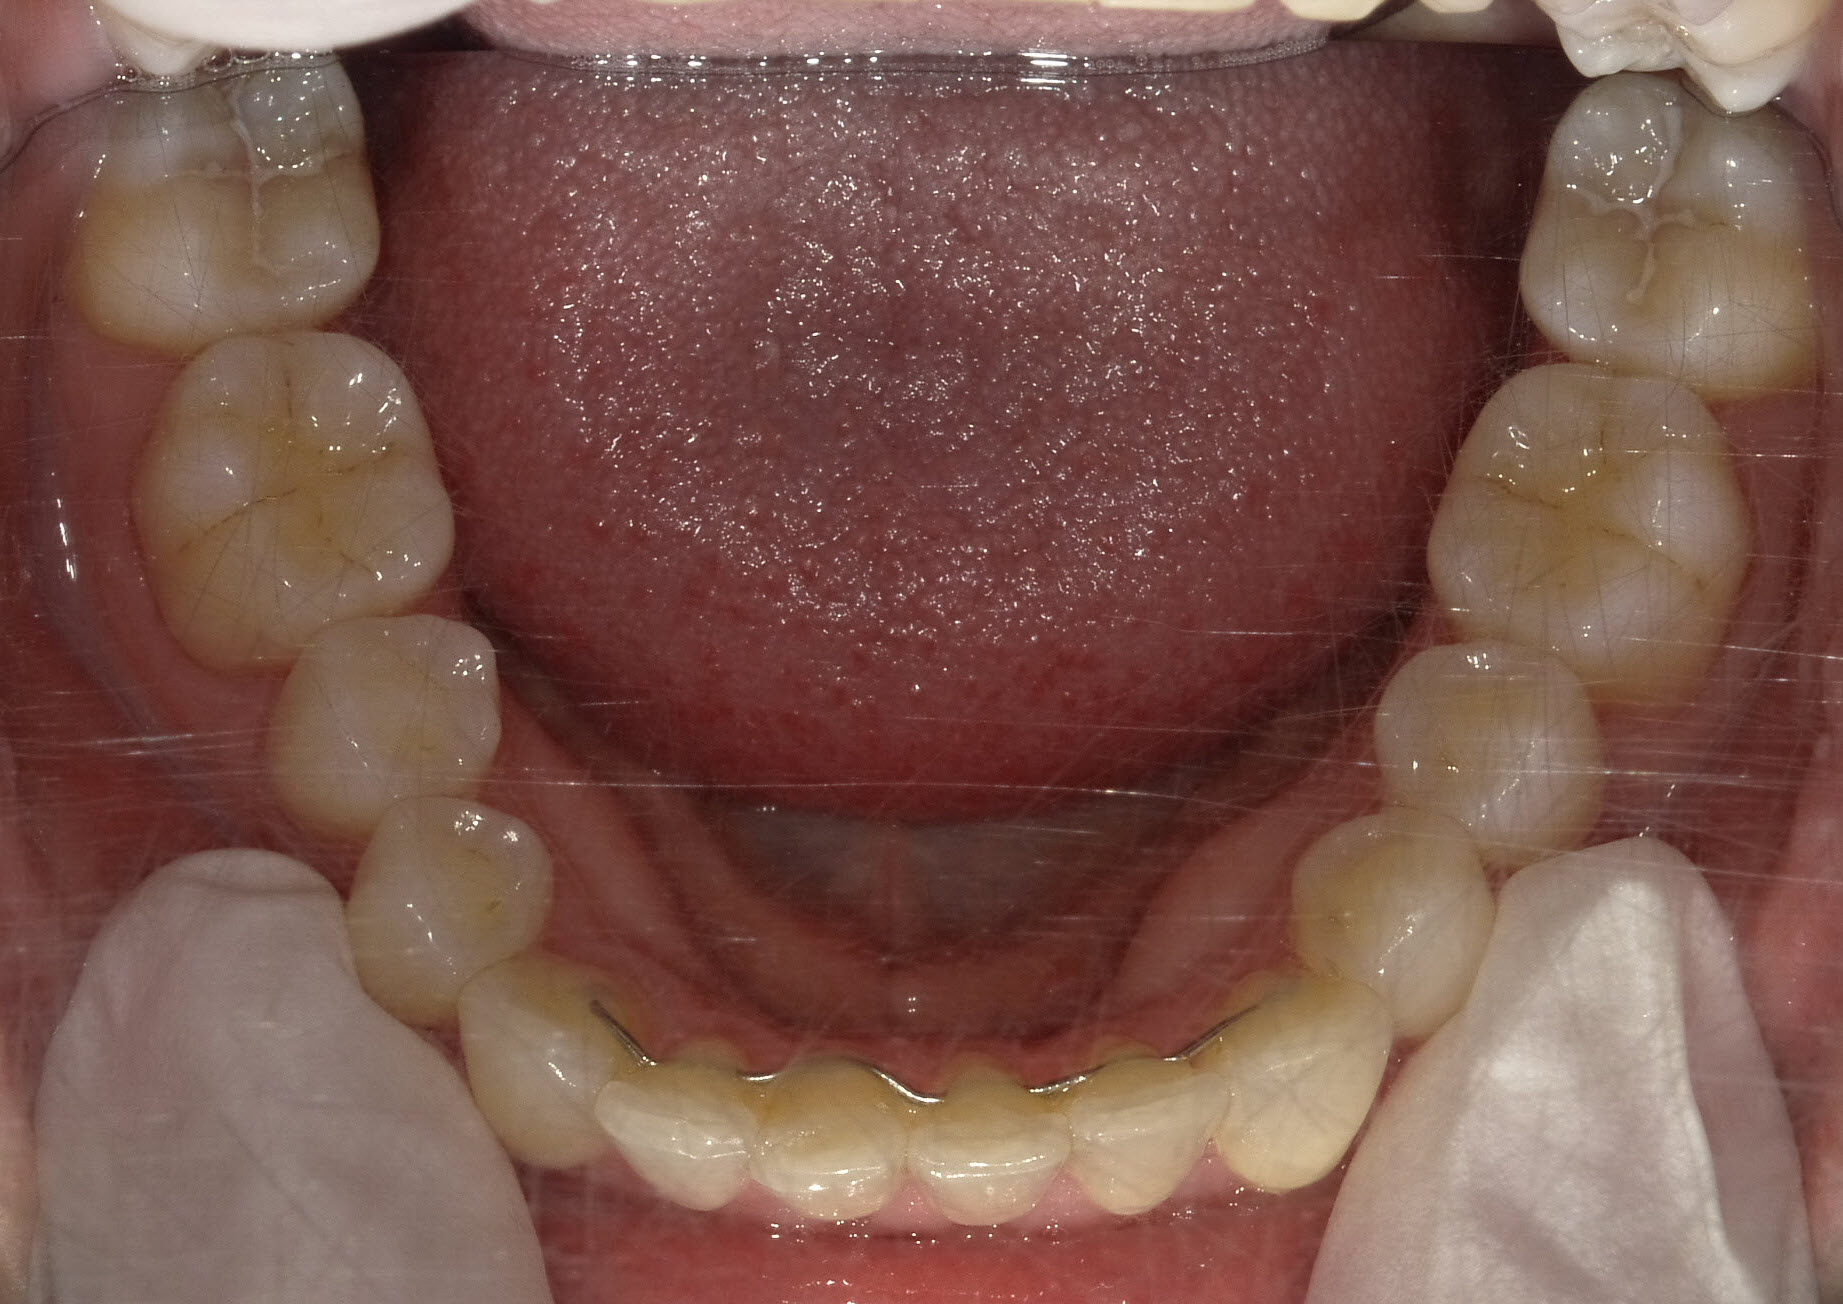

Sehr gute Stabilität nach 12 Jahren